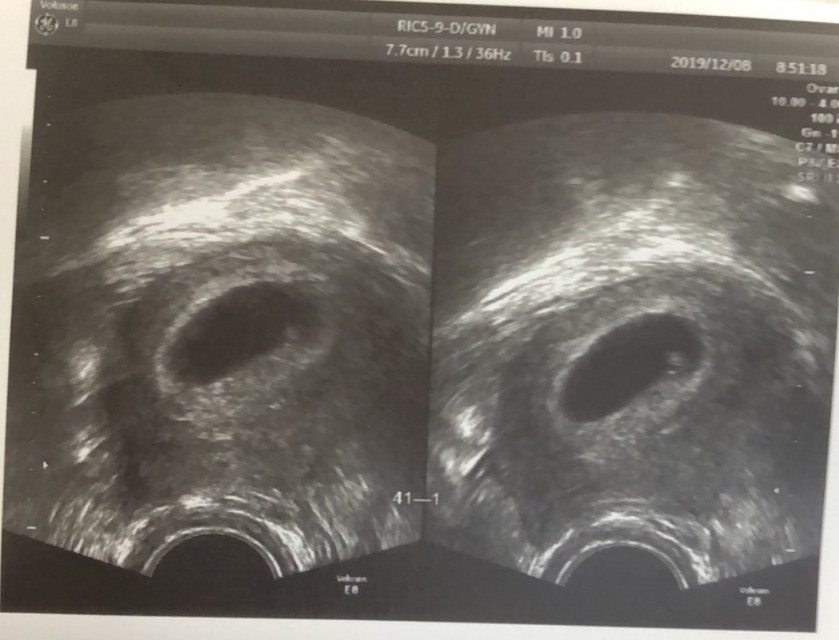

在胚胎移植大约4周后会进行一次B超检查,主要是了解下胚胎发育情况,如果没有发现宫内及双侧附件区孕囊的声像,则验血HCG值,若HCG较孕周明显下降甚至转阴性,那说明发生“生化妊娠流产”。孕妇可能会伴有暗红色或鲜红色的阴道出血,甚至月经来潮。